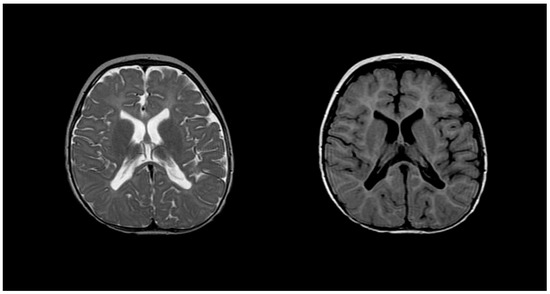

2.2. Metachromatic Leukodystrophy